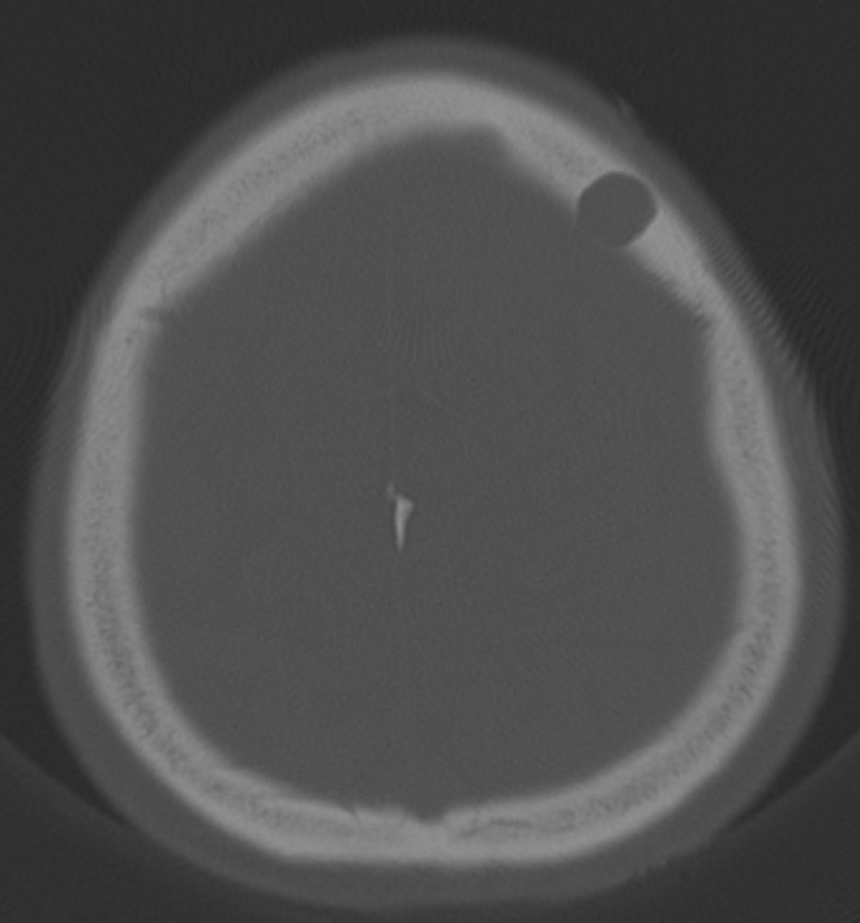

Arachnoid granulations (Pacchionian granulations) are cerebrospinal fluid-filled projections that extend from the subarachnoid space through openings in the dura into the venous sinuses and can be seen macroscopically. Their incidence varies from 0.3% to 55%. Arachnoid granulations are usually seen in millimeter dimensions, but may grow to fill the dural sinuses or arch the inner table[11]. In addition, intraosseous arachnoid granulations can sometimes extend to the inner table of the bone, causing scalloping, remodeling or bone erosion of the inner table[12]. The prevalence of arachnoid granulations increases with age, but there is no difference in gender distribution. Arachnoid granulations with a slight left hemispheric predominance are found in the dural venous sinuses, most frequently in the transverse sinuses and especially in the middle or lateral parts. The second most common location is the superior sagittal sinus, but they can be found anywhere in the dural venous sinuses. Arachnoid granulations are usually detected incidentally. If they fill and expand the dural sinuses, causing partial sinus obstruction, they may cause symptoms of increased intracranial pressure due to venous hypertension. They are usually associated with headaches. Arachnoid granulations may be seen as radiolucent areas on plain radiography of the skull or may cause compression on the inner table of the skull. On CT imaging, arachnoid granulations can be seen as sharply demarcated, hypodense structures in close relation to the dural venous sinus. On MRI, they usually show hyperintense signal on T2-weighted images and hypointense or isointense signal on T1-weighted images compared to brain parenchyma (Figure 1). On CT angiography, MR angiography or catheter angiography imaging, arachnoid granulations appear as oval or round filling defects in the dural venous sinuses during the venous phase[11]. Recent advances in radiology have made it possible to identify brain herniations into the arachnoid granulation by improving image quality with higher resolution and thinner slice three-dimensional T1-weighted and T2-weighted MRI sequences (Figure 2). Brain herniation into the arachnoid granulation is rare in the literature, and the incidence of brain herniation into the calvarial or dural sinuses has been reported to be 0.32%[13]. Arachnoid granulations may be confused with pathological processes in the dural venous sinuses[11]. In the differential diagnosis of arachnoid granulations, venous sinus thrombosis, dural-based tumors, or structures such as septa and fat that may cause filling defects in the dural venous sinuses should be considered[12]. Dural sinus thrombosis usually fills an entire sinus segment or several sinuses and may extend to the cortical veins, whereas arachnoid granulations appear as focal and well-defined defects. Fresh thrombus in the dural sinuses are hyperdense on CT and hyperintense on T1-weighted MRI. Differential tumor diagnosis can be made based on its shape, lack of contrast enhancement and diffusion restriction[11].